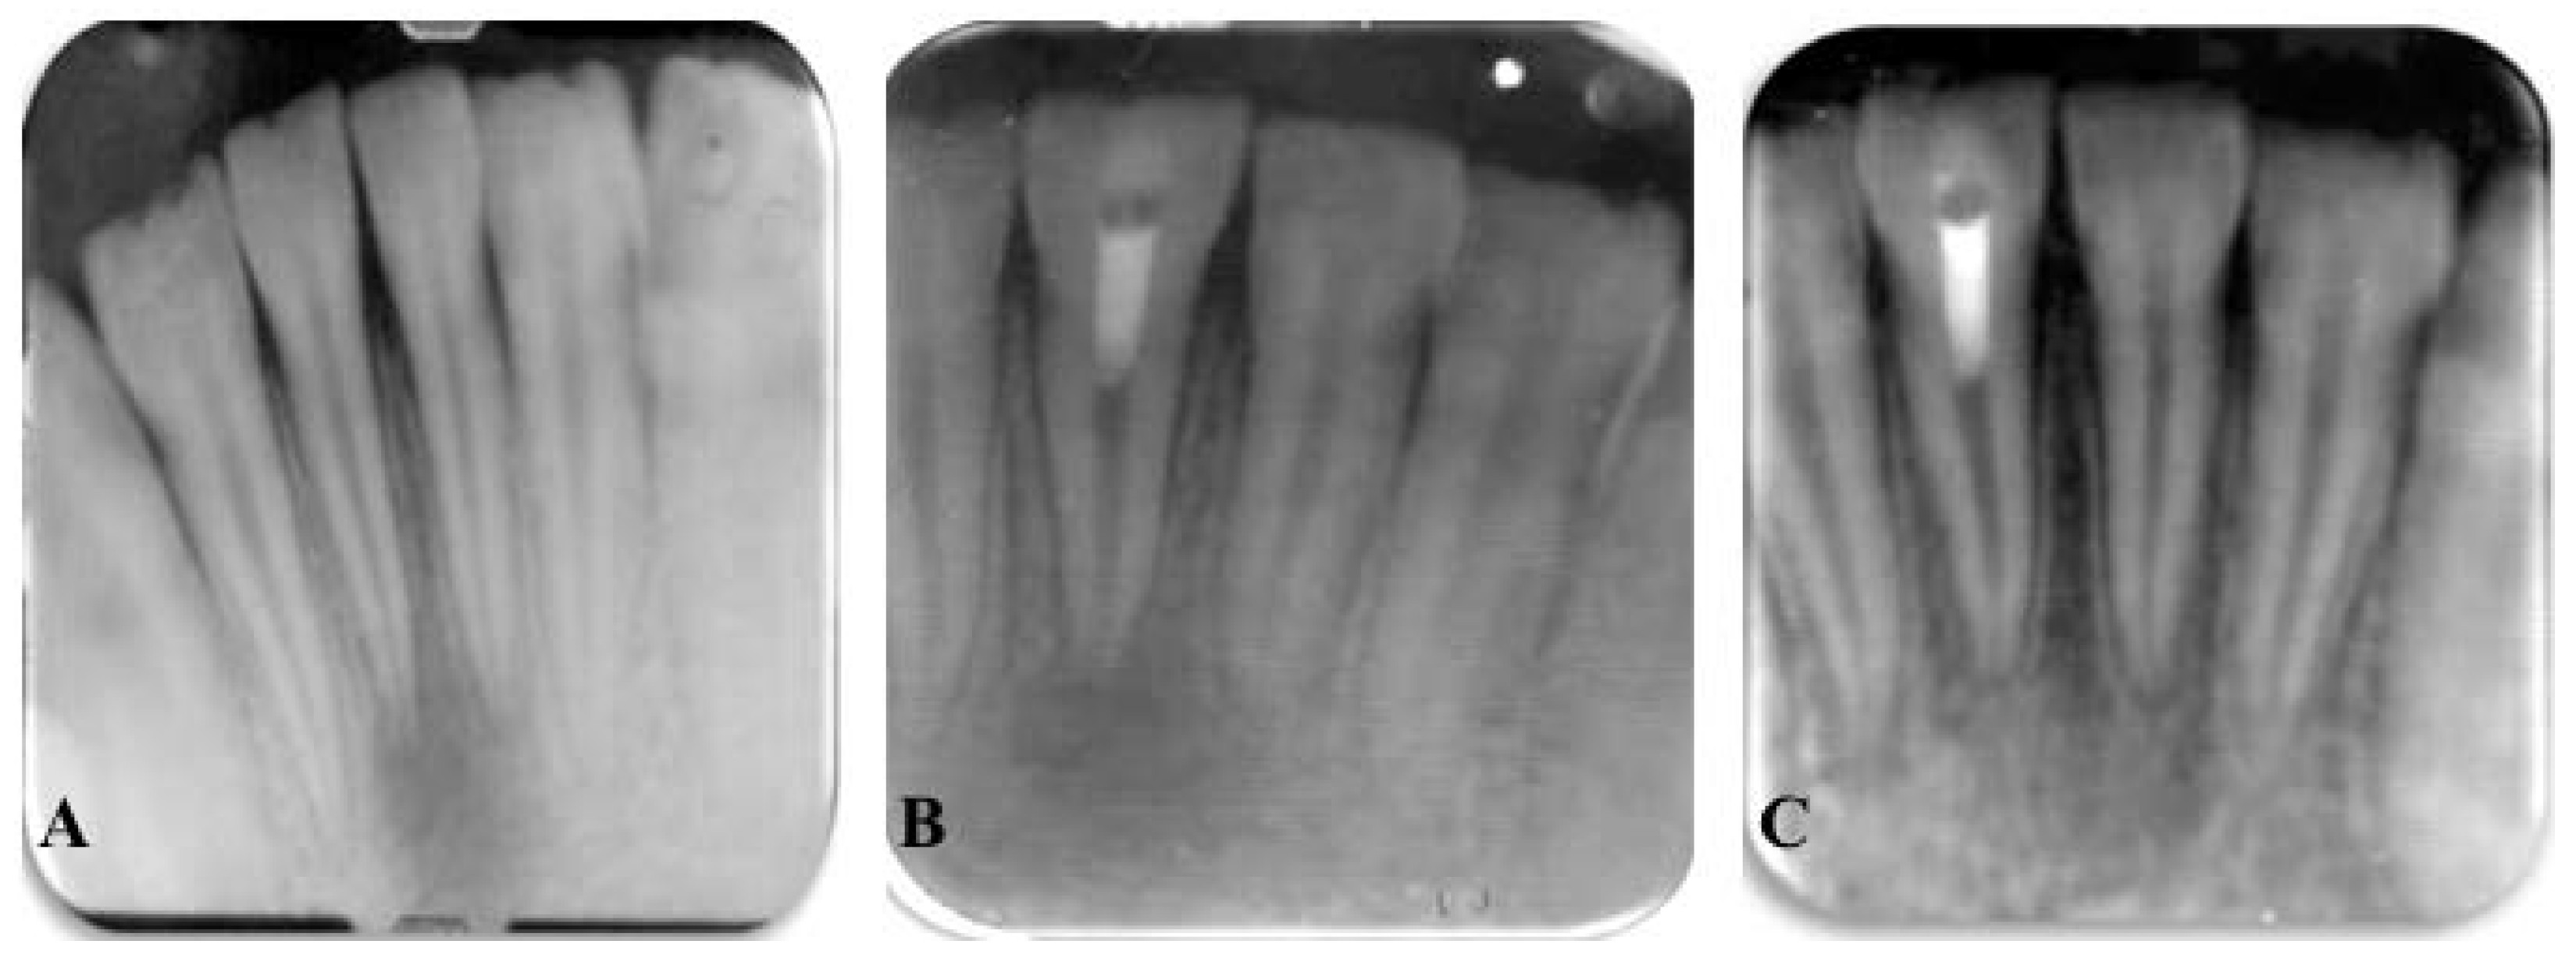

8. Treatment of Immature Permanent Teeth with Necrotic Pulps

- Chen, M.Y.; Chen, K.L.; Chen, C.A.; Tayebaty, F.; Rosenberg, P.A.; Lin, L.M. Response of immature permanent teeth with infected necrotic pulp tissue and apical periodontitis/abscess to revascularization procedures. Int. Endod. J. 2012, 45, 294–305. [Google Scholar] [CrossRef] [PubMed]

- Saoud, T.M.A.; Zaazou, A.; Nabil, A.; Moussa, S.; Lin, L.M.; Gibbs, J.L. Clinical and radiographic outcomes of traumatized immature permanent necrotic teeth after revascularization therapy. J. Endod. 2014, 40, 1946–1952. [Google Scholar] [CrossRef] [PubMed]

- Shin, S.Y.; Albert, J.S.; Mortman, R.E. One step pulp revascularization treatment of an immature permanent tooth with chronic apical abscess: A case report. Int. Endod. J. 2009, 42, 1118–1126. [Google Scholar] [CrossRef] [PubMed]